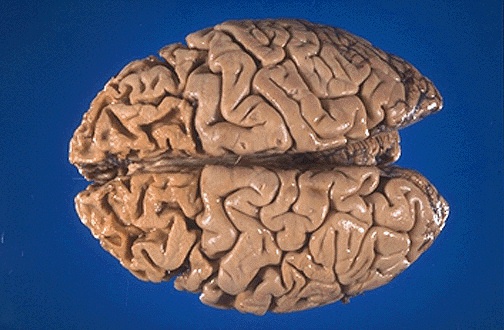

The marked atrophy of Pick disease, a senile dementia similar to that of Alzheimer disease, produces"knife-like" thinning of the gyri in frontal lobes and temporal lobes. As seen from the vertex, the frontal lobes here are markedly thinned.